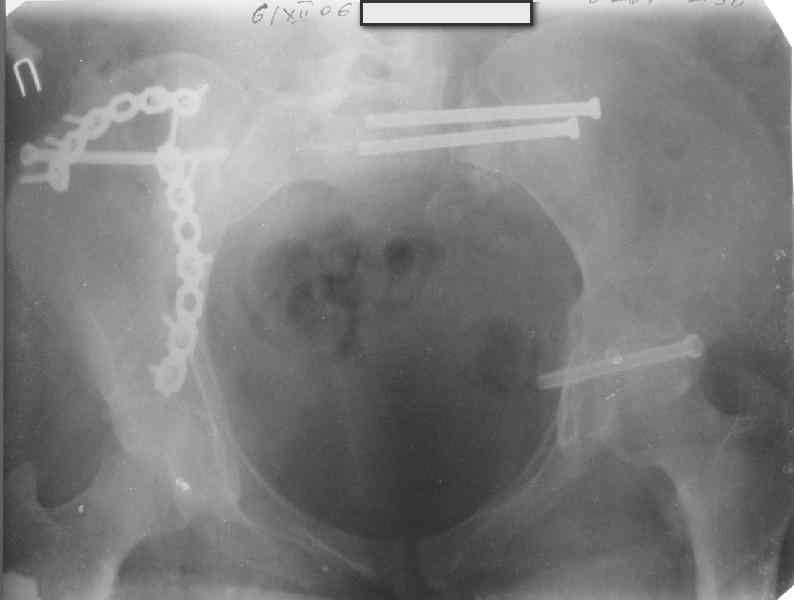

Здравствуйте, коллеги. Какие будут мнения по поводу лечения представляемой больной?

Молодая девушка 19 лет, травма 1 год назад, тогда же прооперирована.

В настоящее время имеются ноющие боли в области крестца слева, нарушение походки, ощущение неуверенности, слабости в левой нижней конечности, неврологически -непостоянные парестезии в левой нижней конечности. Ходит с дополнительной опорой, страдает от ожирения.

В приложении снимки при поступлении и послеоперационные год назад.

Могу сказать одно: миграция винтов и нестабильность синтеза левого подвздошно-крестцовогоо сочленения очевидна.

Забыл добавить, что ИХМО показан реостеосинтез более длинными винтами, с более широкой резьбой, с фиксацией за правое подвдошно-крестцовое сочленение.